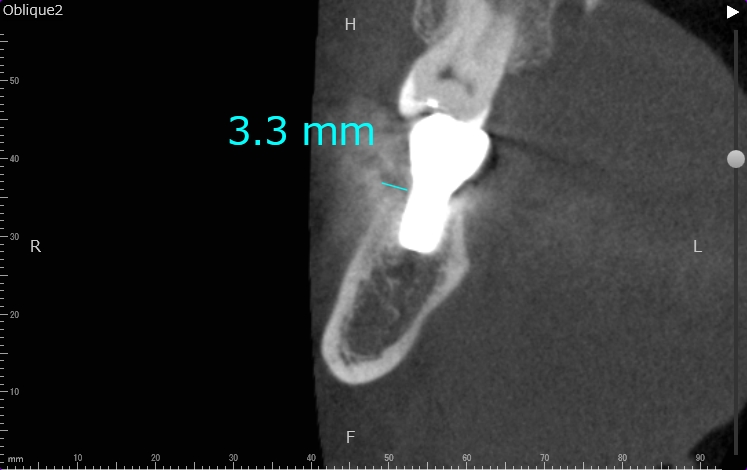

歯科用CTによる精密な検査

当院では必ず精密検査として、歯科用CTによる撮影を行います。顎の骨の状態、血管・神経の位置を正確に把握することで、手術の安全性が高まります。

CT画像は、インプラントの埋入のシミュレーションにも使用します。

2検査・診断

虫歯や歯周病の検査、レントゲン検査、CT検査などを行います。CT検査は、顎の骨の状態、血管・神経の位置を正確に把握し、シミュレーションをするために不可欠な検査となります。